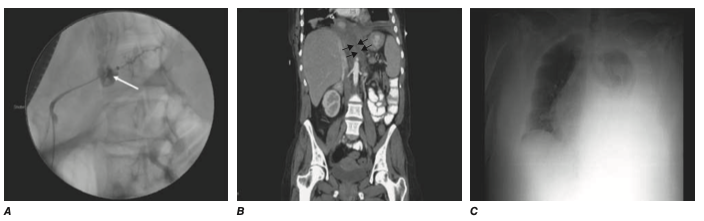

임상증상과 영상 소견 (CT상 acute necrotic collection 내부의 공기음영)으로 진단

췌관 파열

임상양상: 점점 심해지는 복통, 흉수/복수

pleural/ascitic fluid 의 high amylase level

MRCP 또는 ERCP

치료: bridging pancreatic stent